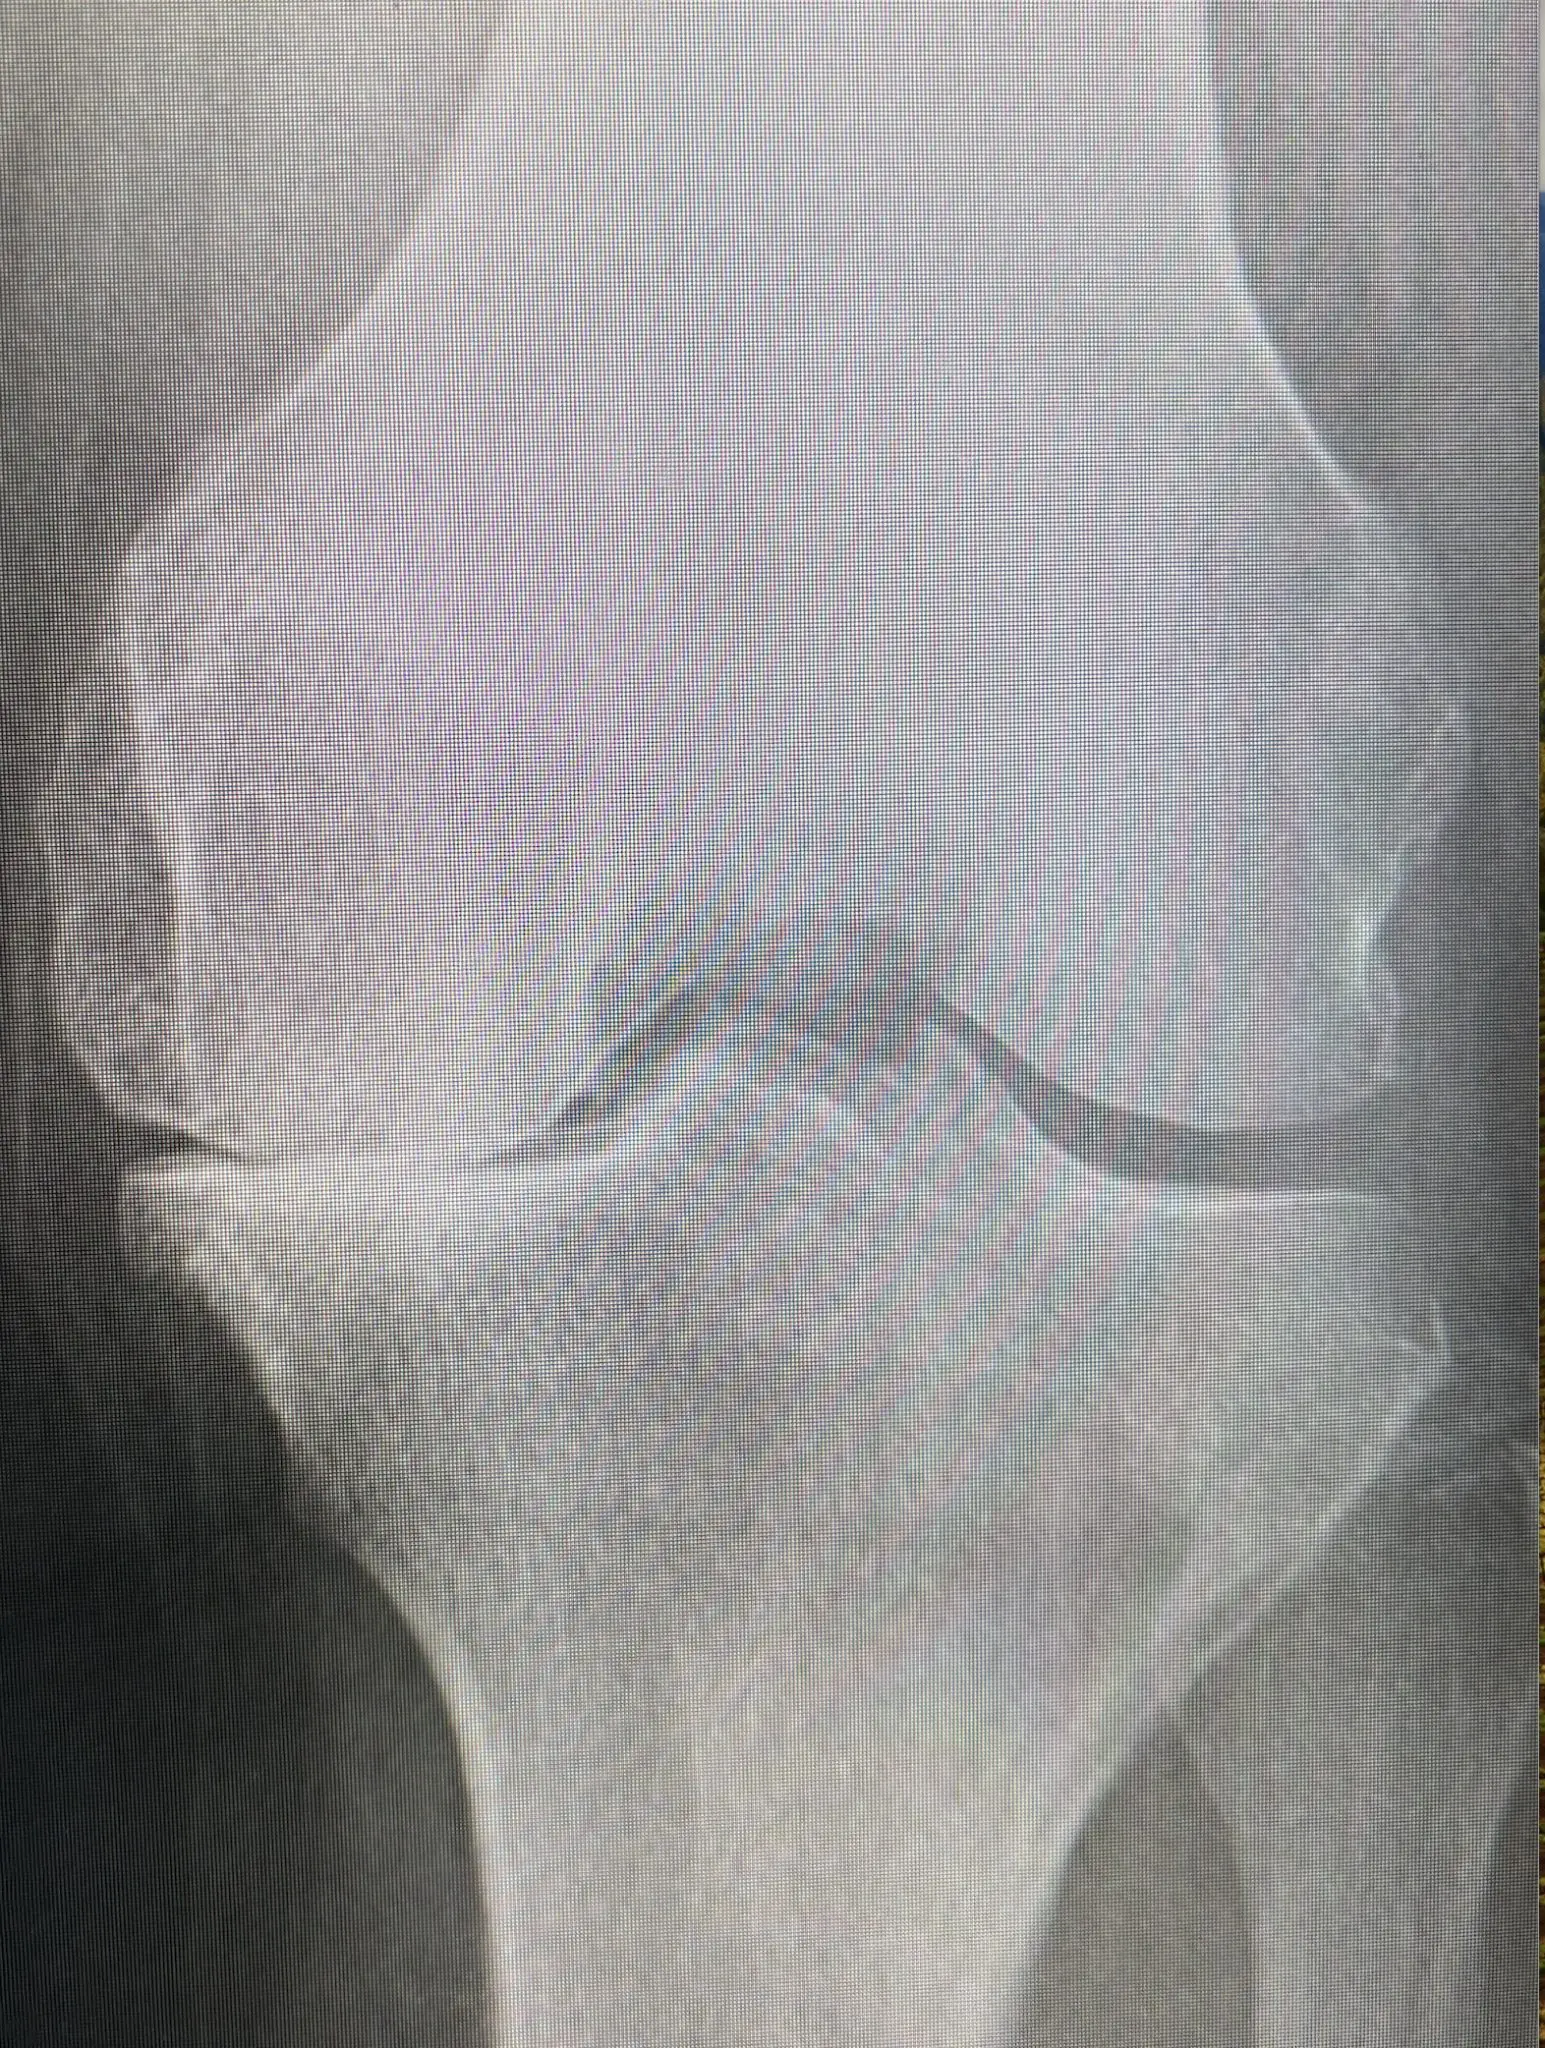

変形性膝関節症(へんけいせいひざかんせつしょう)は、膝の関節軟骨がすり減っていくことで生じる疾患です。この症状は高齢者に多く見られ、膝の痛みやこわばり、機能の低下を引き起こします。今回は、変形性膝関節症の原因や症状、治療法、予防策について詳しく解説します。

変形性膝関節症は、膝関節の軟骨が徐々にすり減っていくことにより、骨同士が直接擦れ合うようになる病気です。この擦れ合いにより、関節に炎症が起こり、痛みや腫れを引き起こします。関節の変形が進行することで、膝の可動域が制限され、日常生活に支障をきたすことがあります。

変形性膝関節症の治療は、症状の進行度合いに応じて異なりますが当院では保存療法として、インソール(装具)、ヒアルロン酸、そして理学療法の3本柱をしてダメならはPRPという再生治療を進めています。ただ、上の写真の方のように保存では難しい症例やPRPをしても効果がないだろうと思われるレベルの方はすぐに手術を進めさせていただき他院へ送らせていただいてます。